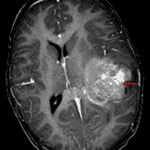

Age: 3

Sex: Male

Indication: Speaking difficulty, imbalance

Atypical teratoid/rhabdoid tumor (AT/RT)